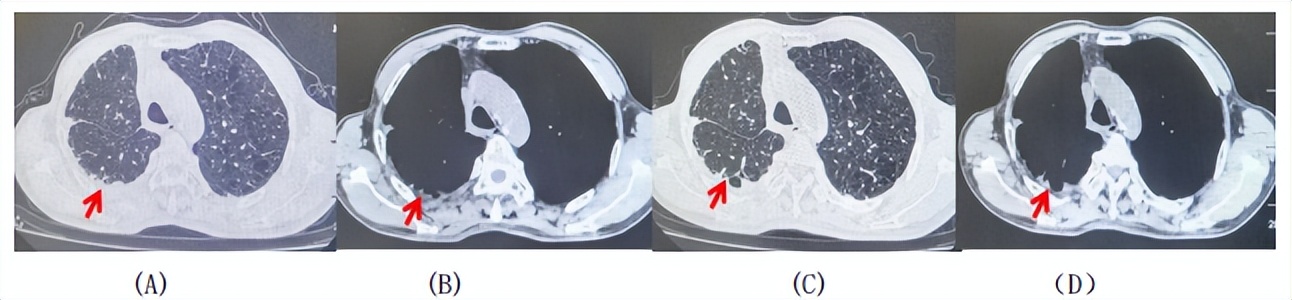

69岁男性,无糖尿病、高血压、心脏病等基础疾病,无吸烟、饮酒史,无肿瘤家族史。2023.06.07行胸部CT检查:右肺上叶胸膜下见肿物影,大小约33mm×22mm,边缘可见分叶,考虑恶性病变可能性大,双肺间质改变(如图1)。2023.06.14行“单孔胸腔镜下右肺上叶切除、肺门及纵隔淋巴结清扫、胸膜粘连松解术”;术后病理:(右肺上叶)腺癌(低分化,实体型占60%,不良腺体占40%),局灶伴神经内分泌标记表达(CD56、Syn),可见STAS及胸膜侵犯,未见确切神经侵犯及脉管内癌栓;(气管切缘)净;(淋巴结)未见转移癌0/26(2组0/2;4组0/6;7组0/2;对侧7组0/8;10组0/2;11组0/3;12组0/2;13组0/1)。术后分期pT2aN0M0 IB期,术后NGS基因检测:无驱动基因突变,PD-L1(22C3)TPS<1%。术后定期复查。

2024.11.19患者出现右侧胸痛,复查胸部CT检查示右侧胸膜肿物,大小约31mmX24mm,右侧4、5肋骨骨质破坏,考虑转移(如图2)。建议患者穿刺活检取病理明确诊断,患者拒绝,经MDT会诊后结合影像学表现及病史考虑为胸膜转移,肋骨转移,分期为rT0N0M1a IVA期,DFS仅仅17个月。2024.12.05起行信迪利单抗联合培美曲塞+卡铂方案治疗4周期,复查胸CT评效PR(如图3)。之后给予信迪利单抗+培美曲塞维持治疗6周期,期间复查CT评效PR(如图3)。目前信迪利单抗+培美曲塞维持治疗中,截止至目前PFS约为8个月,治疗期间未出现明显毒副反应。

图1:患者手术前(2023.06)胸部CT肺窗及纵隔窗

图2:患者胸膜及肋骨转移(2024.11)胸部CT肺窗、纵隔窗及骨窗

图3:患者免疫联合化疗治疗后胸部CT,(A、B)图展示信迪利单抗联合培美曲塞+卡铂治疗

4周期(2025.02)疗效,(C、D)图展示信迪利单抗+培美曲塞维持治疗6周期(2025.07)疗效